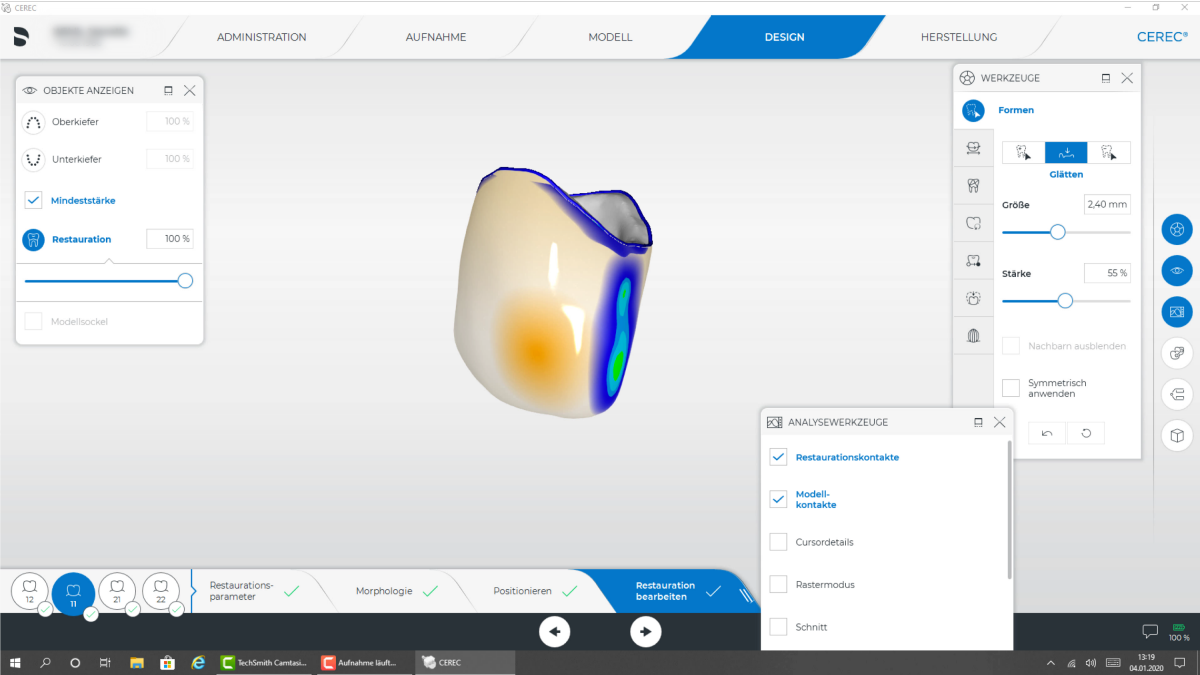

53 éves páciens érkezett a rendelőmbe problémákkal a front fogainál. A vizsgálat során nem megfelelő töméseket találtunk a 12-22-es fogak között és egyenetlen ínyvonalat a 12 és 11-es fogaknál. A páciens nem egyezett bele a sebészeti beavatkozásba. Továbbá az incizális szélek több helyen erodálódtak és egyenetlenek voltak. A páciens szenvedett ezektől az esztétikai problémáktól és emiatt ritkán mosolygott. Úgy terveztük együlésben helyreállítjuk ezt a négy fogat egyéni koronákkal. A fogszínnek megfelelően a lítium-diszilikát kerámia mellett döntöttem. A 23-26 fogak restaurációját a későbbiekben hozzáigazítjuk a páciens kérésére, az egységes esztétikáért. A pótláshoz a klasszikus CEREC protokollt követtem; a virtuális modellen alig korrigáltam az automatikusan megjelölt preparációs határokon és intraorálisan összehasonlítottam. Ezután a szék mellett megterveztem a pótlást. Mind a négy koronát sikeresen kifaragtuk a CEREC Primemill-lel. Ez egyesével körülbelül 10 percig tartott Fine Mode-ban. A koronák a terveknek megfelelően simák és esztétikusak lettek. Lakkozást és individualizálást követően a koronák a CEREC SpeedFire-ben szinterezhetők. A még jobb optikai transzparenciáért a zománcot kék kerámia festéssel szimuláltuk. Szinterezés után a restaurációkat ellenőriztük a szájban, majd előkészítettük foszfor- és hidrofluor savval, valamint szilanizáltuk és két részletben adhezíven ragasztottuk kofferdám és teflonszalag mellett (a kontaktpont izolálásához) Prime&Bond Active-val (Azonos termék Prime&Bond Universal) és Calibra Cerammal, majd eltávolítottuk a felesleget. Az okklúzió ellenőrzése után az új koronák megkapták a végső polírozást. Végül a teljes kezelés kevesebb, mint 4 óráig tartott és a páciens nagyon elégedett volt új, gyönyörű mosolyával.

- A rendszer közel tökéletes preparációs határt mutatott

- Minimális korrekció a preparált határ berajzolásán

- Preparáció analízise a potenciálisan problémás területek azonosításához. Ebben az esetben nem volt ilyen

- A kialakítás labiális irányból

- A kontaktpont tervezése